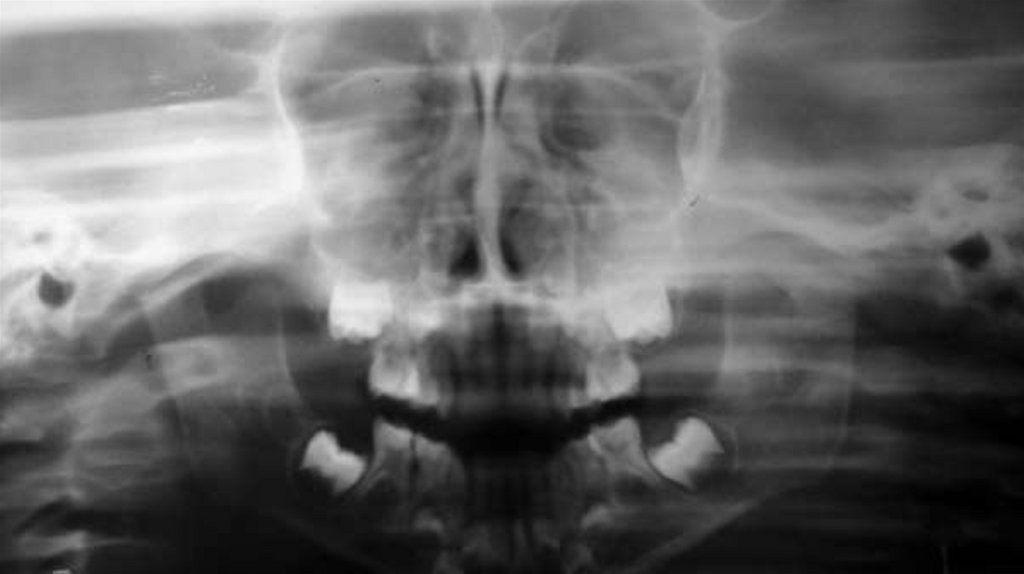

Были собраны подробные истории болезни, проведены

клинические и рентгенографические исследования, такие как

ортопантомография, окклюзионная рентгенография и

внутриротовая периапикальная рентгенография . После

тщательной оценки был поставлен диагноз типа перелома и был

составлен план лечения для каждого пациента.